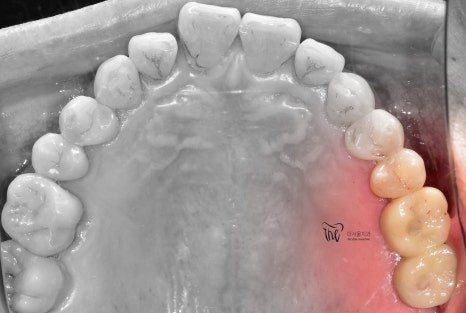

구강내 사진에서도, 아직 잔존 치조골이

충분히 남아있는 것은 확인이 되나

이는 정확히 CT를 찍은 뒤에

네비게이션 임플란트 진단을 해야

정확히 말씀드릴 수 있는 상황이였습니다.

이제, 구강 내 사진에서 보실 수 있는 것 처럼

어금니 빠짐 자리에 새로운 크라운이 자리를

잡으면서 이제 구강 내에 빈 곳이 없어졌네요.